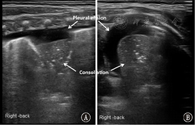

本组MAS患儿的肺脏超声主要表现(表1):(1)肺实变伴支气管充气征:见于所有患儿,重度患儿通常为范围较大、且边界不规则(锯齿状边缘)的实变区(图2,图3,图4);而轻度患儿则以小范围的局限性实变为主要表现(图5);但双侧肺脏实变范围的大小可以不同,而且同一侧肺脏野可以存在大小不同的实变区(图4,图5,图6)。(2)胸膜线异常与A-线消失,见于所有患儿,胸膜线异常表现为病变区胸膜线消失或增粗模糊(图2,图3,图4,图5,图6)。(3)肺不张,是严重肺实变的表现,见于重度患儿,本组12例(17.9%)(图7),严重大面积肺不张时可在实时超声下见到肺搏动和动态支气管充气征。(4)胸腔积液,见于9例(13.4%)患儿(图7)。(5)B-线或AIS,在实变区以外肺野则以AIS或B-线为主要表现。

注:MAS:胎粪吸入综合征;A:探头与肋骨垂直扫描;B:探头与肋骨平行扫描 MAS:meconium aspiration syndrome;A:the probe was perpendicular to the ribs;B:the probe was parallel to the ribs

MAS具有典型的肺脏超声影像学改变。主要特征如下:(1)肺实变伴支气管充气征,见于所有患儿。通常重度患儿实变范围较大、边界不规则呈锯齿状,支气管充气征也较为明显;而轻度MAS则为较小范围的局灶型实变。(2)双侧肺脏或同一侧肺脏不同肺野病变性质与程度的不一致性,双侧肺脏可有范围不同的实变区,同一侧肺脏不同肺野也可以存在大小不同的实变区。(3)肺不张,见于少数重症患儿,更为严重者在实时超声下可见肺搏动或动态支气管充气征。(4)胸膜线异常,表现为病变区胸膜线消失或增粗、模糊。(5)A-线消失,所有患儿在实变区和非实变区均不见A-线。(6)B-线或AIS,非实变区肺组织在超声下常表现为B-线或AIS。(7)胸腔积液,轻度或重度MAS患儿均可有胸腔积液,本组见于13.4%的患儿。但上述超声表现也可见于RDS、肺不张和TTPN等肺病,虽均非MAS的特有改变,但均有各自的特点,超声很容易对它们做出诊断和鉴别诊断[4,5,6,7]。但在肺炎、尤其重度肺炎时,肺脏超声也表现为边界不规则的大面积肺实变[7,15],如无一定经验,仅靠超声表现有时难以将二者准确区别。因此,在借助超声诊断MAS与重症感染性肺炎时,往往需要结合病史。